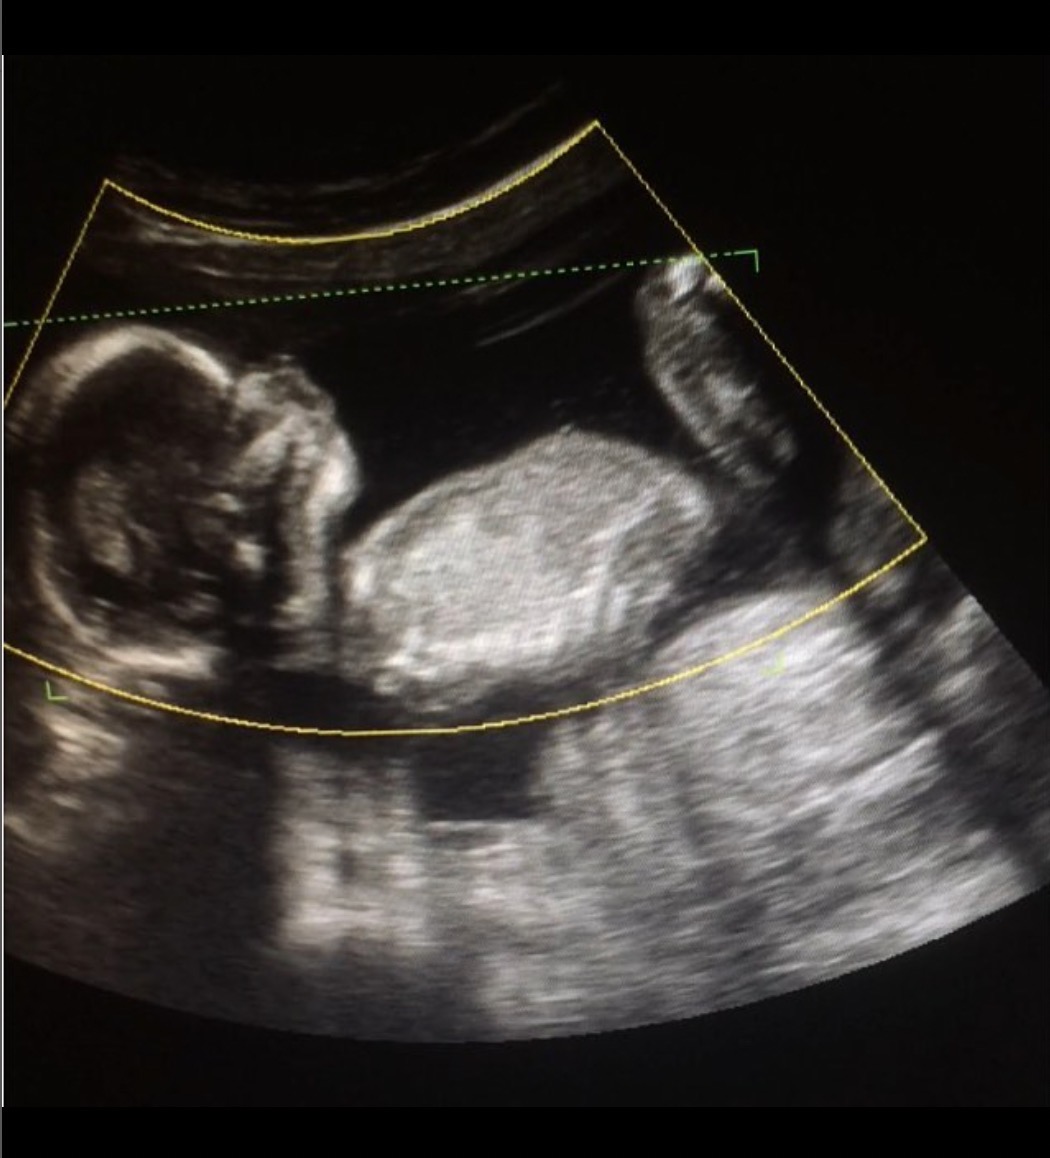

Just got home from our 13 week scan. Would love your thoughts on whether baby is pink or blue! The nub looks girly to me but then later on in the scan the sonographer went down around in a type of potty shot and I thought I saw something between the legs, so now I'm not so sure (didn't get a photo when she went in for the potty shot, she said it was too early to tell)... are potty shots reliable for gender at 13 weeks? If I hadn't seen that potty shot I'd have guessed girly?

I read the nub thread before we went and didn’t take my eyes off the screen as the somographer scanned me, and didn’t see any stacking at all, just those lines (I remember clearly seeing stacking and a little triangle with DS2 at his 12 week scan). Baby was quite curled up during these shots.

Added some scull shots in case anyone knows anything about scull theory! Xx